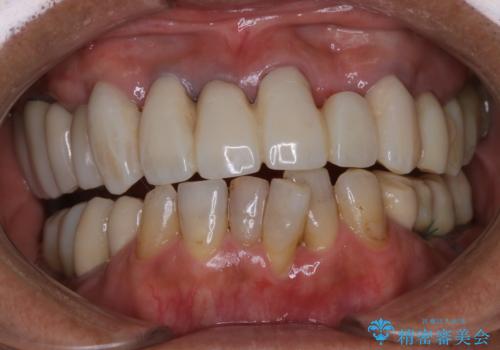

表のワイヤー装置で矯正中にPMTCで綺麗にお掃除

担当医 歯科衛生士